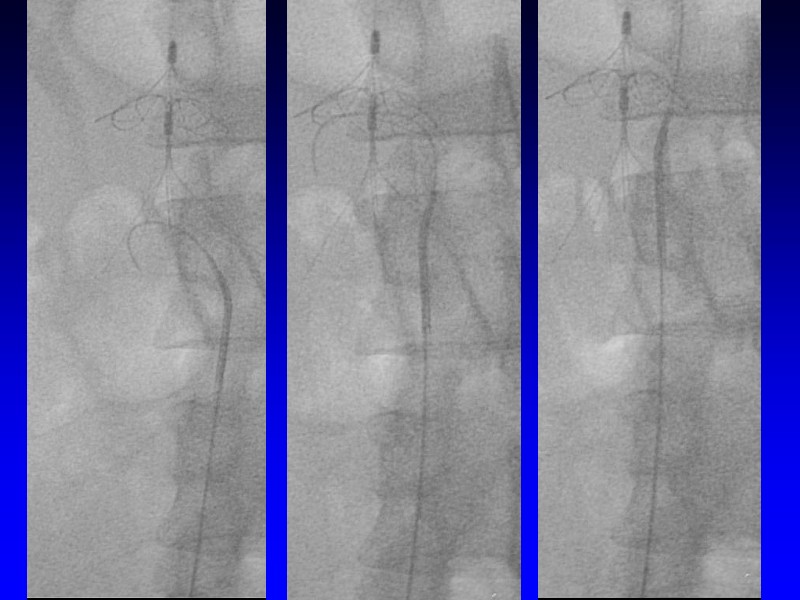

Slide 20 of 29